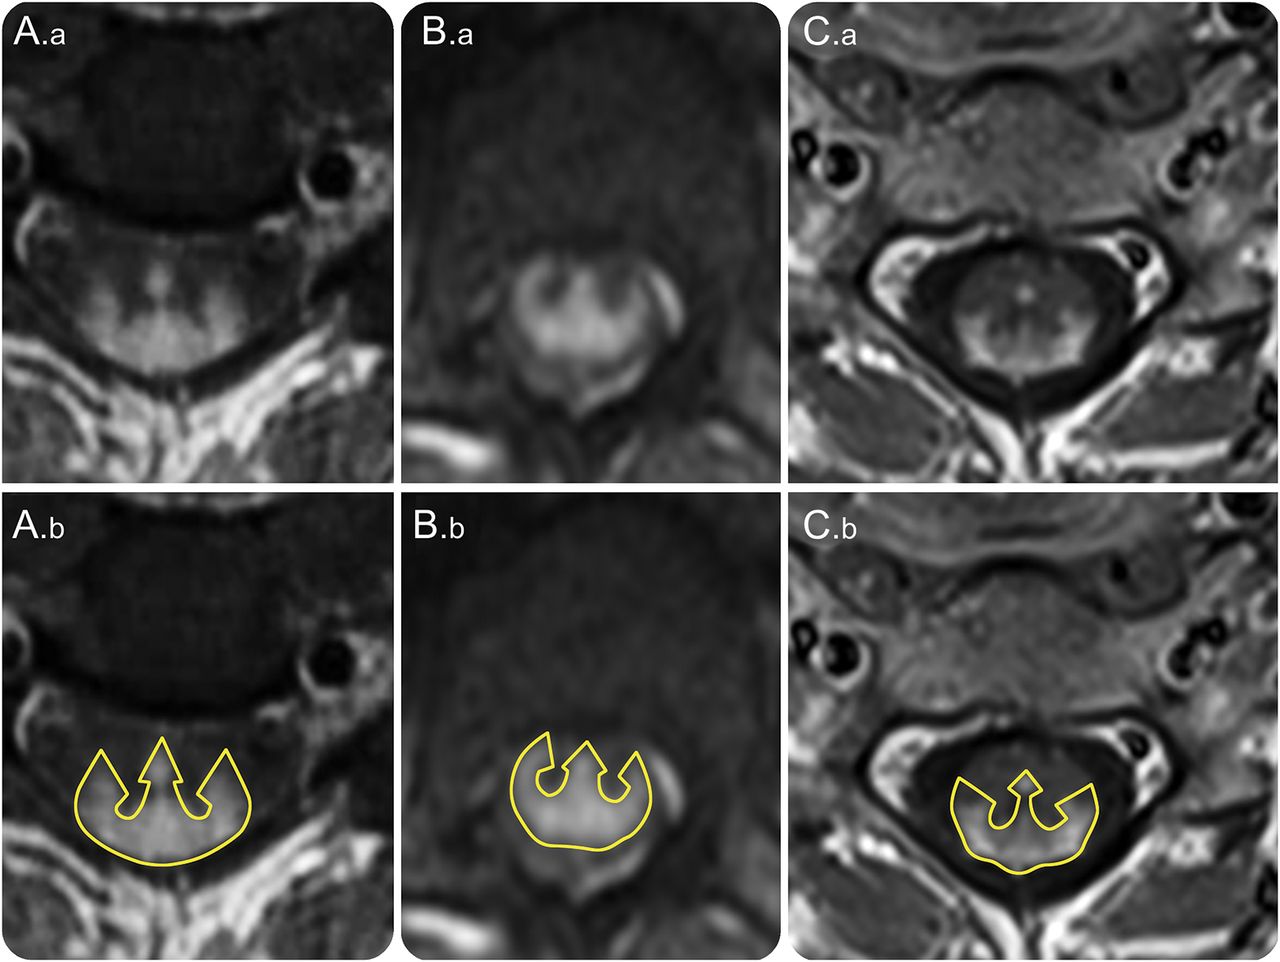

新月形的分层后单纯的增强伴随着中央管增强导致一个三管齐下的外观(。a、B。a, C。a) resembling a trident head (A.b, B.b, C.b).